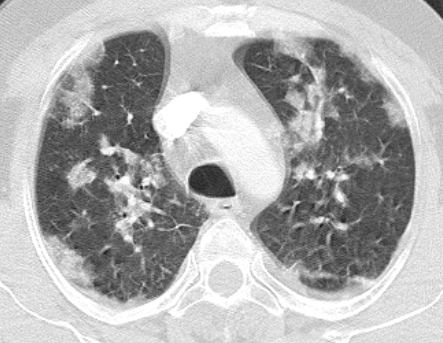

A 40-year-old male patient was admitted to our clinic with complaints of persistent cough for 10 days, phlegm, respiratory distress, fever at intervals, knee pain, and fatigue particularly increased for the past two days. During physical examination, the patient was conscious with poor orientation and cooperation, and was agitated and drowsy. His medical history was able to be obtained from his relatives due to his limited cooperation and orientation. He had a medical history of 20-packyears of smoking and brucellosis 13 years prior. He had a fever of 38.5°C, heart rate was 113 bpm, blood pressure was 100/60 mmHg, and respiration rate was 32/min. Lung auscultation showed bilateral, widespread crepitant rales in all zones of the lungs. Lung sounds were not present in the right basal lung, and dullness was detected with percussion. Cardiovascular examination findings were normal, except for tachycardia. Abdominal examination showed no signs of defense, rebound, or tenderness. Extremities were normal; however, circulatory impairment and cyanosis were present in the periphery. Laboratory test results were as follows: leukocyte 19,900/mm3, hemoglobin 13.7g/dL, hematocrit 40%, platelet count 270,000/mm3, erythrocyte sedimentation rate (ESR) 88mm/hour, and C-reactive protein (CRP) was 15.1 mg/dL. Arterial blood pressure analysis showed that pH was 7.29, PO2 was 76 mmHg, pCO2 was 22mmHg, HCO3 was 11mmol/L, and satO2:94%. Biochemical analysis of blood showed a Na level of 122mmol/L, aspartate aminotransferase (AST) level of 306 IU/mL, and alanine aminotransferase (ALT) of 143.6IU/mL. Metabolic acidosis was present in the arterial blood gas. A posteroanterior radiograph showed bilateral pneumonic infiltration and pleural effusion on the right side (Figure 1). Thoracic computed tomography (CT) showed multiple opacities and right-sided pleural effusion (Figure 2). Serum agglutination titer for Brucella was 1:320. Pleural fluid obtained on thoracentesis was consistent with exudate and hemorrhagic. Pleural fluid tested positive for Rose-Bengal test. Based on clinical and physical examination findings, the patient was diagnosed with brucellosis with lung and pleural involvement. The patient was initiated on ceftriaxone 2 g bid, doxycycline 100 mg bid, and rifampicin 600 mg once daily. His general condition improved on Day 15 of treatment and did not have fever for five days. He was discharged with the recommendation of outpatient follow-up visits. Doxycycline 100 mg bid and rifampicin 600 mg once daily treatment was scheduled to continue until two months (Figures 3 & 4).

Figure 4

A multi-center study by Pappas reported that 37 (6.9%) of a total of 450 patients with brucellosis had pulmonary involvement with varying clinical manifestations.7 The mean age of this patient group was 53 years with a female-to-male ratio of 1:2. In addition, 35 patients (94.5%) had fever, 25 (67.6%) had coughing symptoms, 10 (27%) had sputum, and seven patients (19%) had respiratory symptoms such as dyspnea. In addition, a retrospective study evaluated a large cohort of 1,028 patients with brucellosis.10 The mean age of the patients was 33.7 years, and the most common clinical and laboratory findings were fever, arthralgia, elevated CRP, and osteoarticular involvement. About 2% of the patients had coughing symptom, while seven (0.7%) had pulmonary involvement in the form of pleurisy. In another prospective study, pulmonary involvement was seen in 11 of 110 patients with brucellosis (10%).11 These patients had clinical symptoms including coughing, phlegm, and shortness of breath, and radiological symptoms including parenchymalnodules, lobar pneumonia, paratracheal lymphadenopathy, and pulmonary involvement such as pleural effusion. Treatment for brucellosis resulted in complete recovery of these symptoms. Similarly, our case recovered with treatment for brucellosis, as confirmed by chest X-ray and thoracic CT.